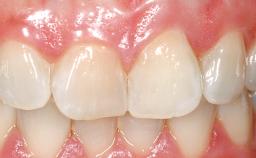

Late Flapless Placement of an Implant in a Maxillary Left Central Incisor Site

Prosthesis Type FDP

Lip Line No exposure of papillae Exposure of papillae Full exposure of mucosa margin

Periodontal Phenotype Low-scalloped, thick Medium-scalloped, medium-thick High-scalloped, thin